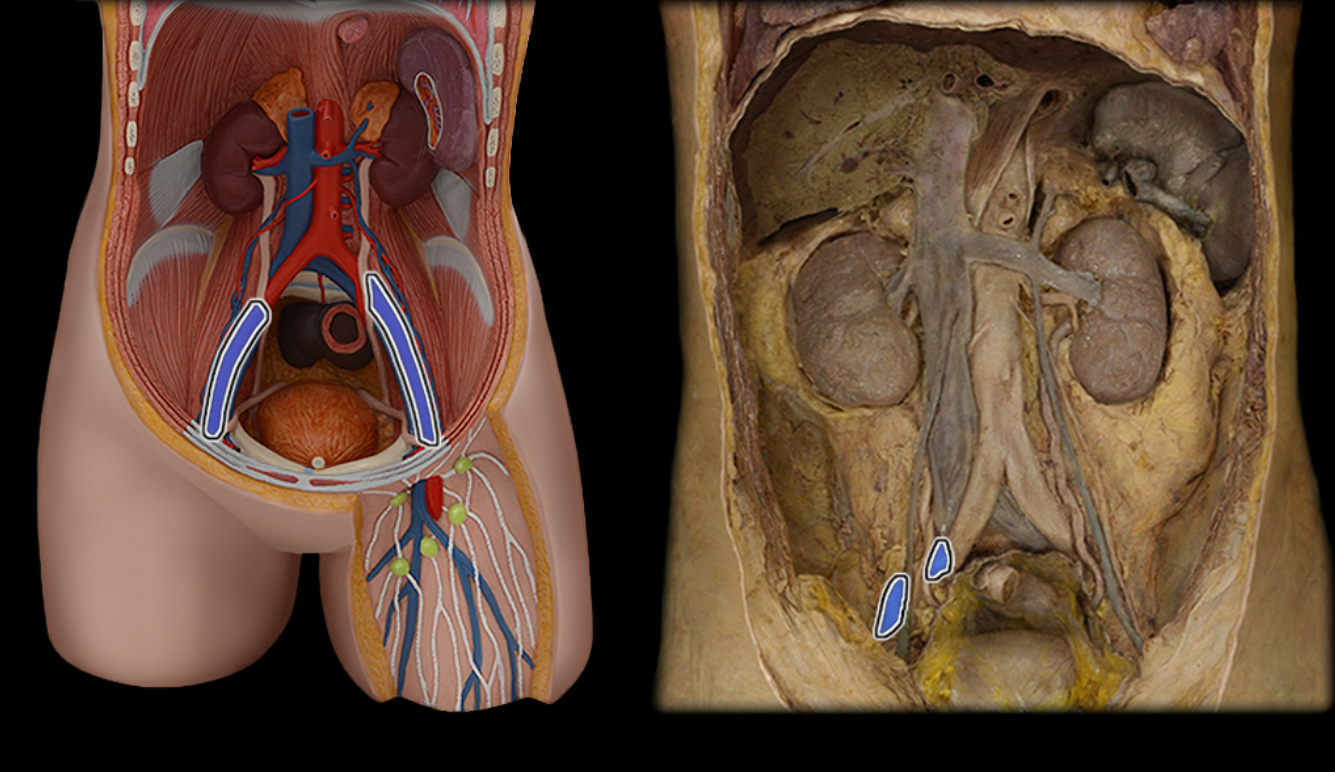

Common iliac a.

Common iliac v.

External iliac a.

External iliac v.

Femoral a.

Femoral v.